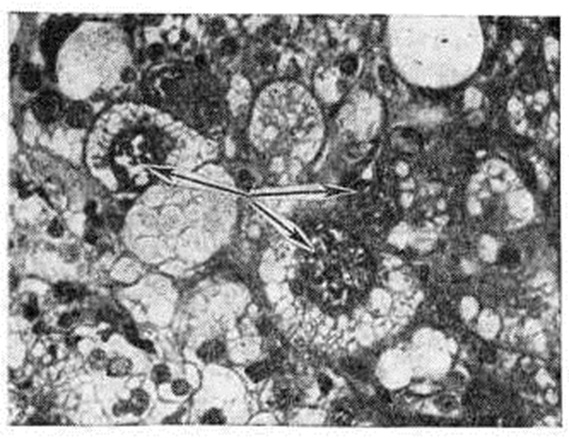

Рисунок 1.

Микроскопическая картина доброкачественной гиберномы: крупные клетки с чёткими границами и центрально расположенным ядром (указаны стрелками).

На разрезе опухоль буроватого цвета с чёткими очертаниями, дольчатого строения. Микроскопически состоит из крупных округлых или полигональных клеток с чёткими границами и центрально расположенными ядрами (рисунок 1). Клетки группируются в ячейки или дольки окружённые нежной стромой. Различают два вида клеток: одни с гомогенной, окрашивающейся в тёмно-розовый цвет цитоплазмой, содержащей небольшое количество жира, другие — мелкозернистые или пенистые, перегруженные липидами (нейтральным жиром, холестерином.